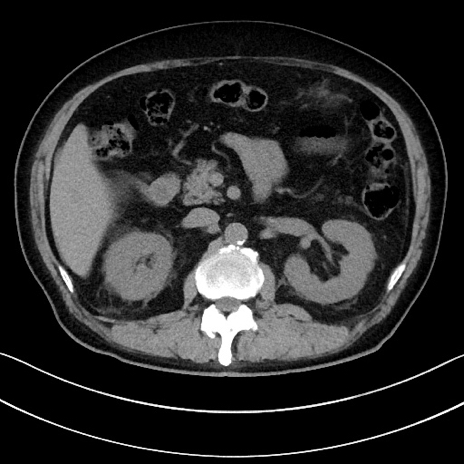

症例15(横断像)

【症例】70歳代男性

【主訴】腹痛

【現病歴】今朝から腹痛あり。全体的に痛い。特に左上の方。排ガスが今日はない。冷や汗が出る。

【既往歴】直腸癌術後

【身体所見】左側腹部〜上腹部に圧痛あり。腹膜刺激症状明らかなではない。軽度反跳痛。左下腹部に術後瘢痕あり。

【データ】WBC 7700、CRP 0.02